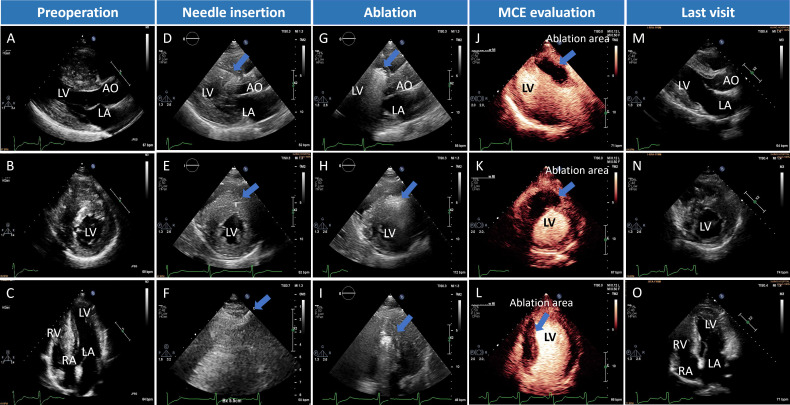

Background: Patients with drug-refractory non-obstructive hypertrophic cardiomyopathy (NOHCM) lack effective invasive treatment options. This study aimed to evaluate the safety and effectiveness of percutaneous intramyocardial septal radiofrequency ablation (PIMSRA, Liwen procedure) in patients with NOHCM and severe septal hypertrophy (≥28 mm).

Method: This single-arm, open-label, prospective study enrolled 20 adult patients with drug-refractory NOHCM between June 2017 and June 2023. Patients underwent PIMSRA and were followed for a median of 15 months. Outcomes included changes in septal thickness, quality of life (Kansas City Cardiomyopathy Questionnaire-12, KCCQ-12) and myocardial function.

Results: No major adverse clinical events occurred within 30 days after the procedure. The maximum interventricular septal thickness decreased significantly from 31.3 mm to 17.4 mm (mean difference: -13.9 mm; 95% CI -15.92 to -11.88). Left atrial volume index and left ventricular mass index also decreased significantly. Improvements in global longitudinal strain and global radial strain were observed, indicating possibly enhanced myocardial performance. KCCQ-12 scores improved from 65.6 to 84.4 (mean difference: 18.78; 95% CI 11.62 to 25.93). Patients after PIMSRA were not found to have an increased risk of arrhythmias such as atrial fibrillation, high-grade conduction block or non-sustained ventricular tachycardia during the follow-up.

Conclusions: PIMSRA was associated with a reduction of myocardial septal thickness and improvement in functional status in patients with NOHCM. The absence of major adverse events is also encouraging, but larger studies with a control arm are needed to confirm long-term safety.